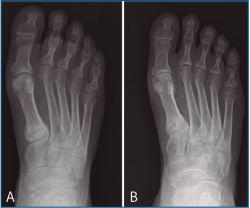

Figura 4. Caso 2. Fractura por estrés de la base del primer metatarsiano del pie derecho pasados 19 meses de la intervención (A). Consolidación de la fractura tras tratamiento ortopédico (B).

Las complicaciones más importantes fueron: en el paciente n.º 2, una fractura por fatiga en el primer metatarsiano y una sobrecarga metatarsal del segundo radio en el pie derecho (tras 19 y 28 meses de la intervención, respectivamente), que se resolvieron utilizando un zapato de balancín y calzado con suela amortiguada.